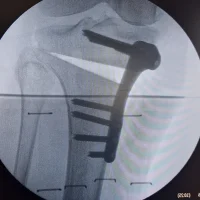

- Chirurgie de l'épaule